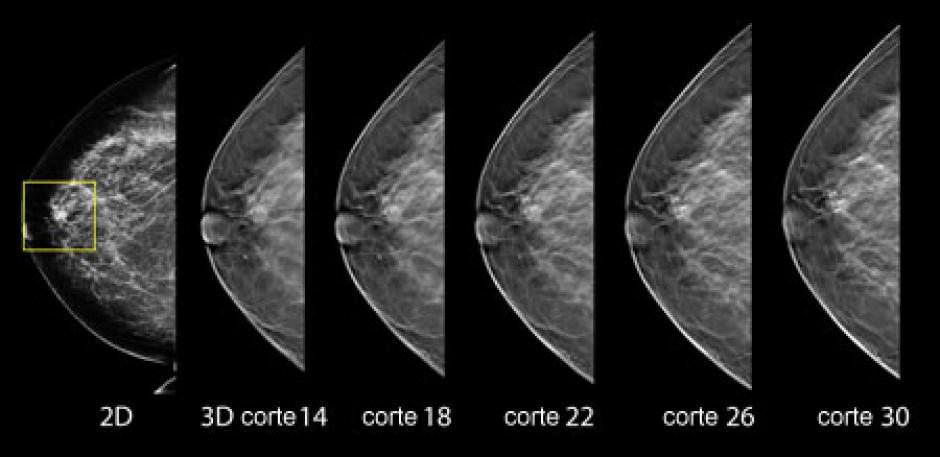

Este sistema que combina mamografía digital e imagenología por tomosíntesis permite obtener imágenes mucho más detalladas y precisas del seno. Son usadas para recrear imágenes de un milímetro de espesor que pueden ser visualizadas en una reconstrucción de la mama en 3D.

La 3D permite mejorar el diagnóstico ayudando a los radiólogos a identificar las estructuras de los senos y ver bien las zonas que quedan borrosas con la mamografía en 2D, que pueden revelar un tumor pero también ocultarlo.